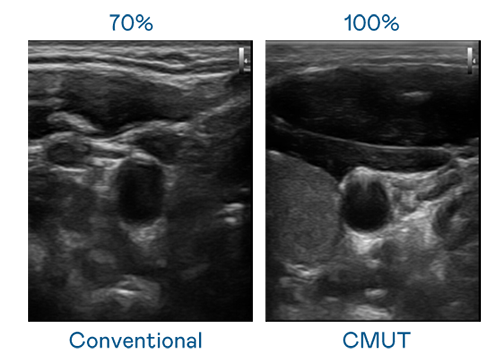

CMUT 技術是一種用電容式微機電元件來產生超音波訊號的技術。與傳統 PZT 壓電式技術相比,CMUT 頻寬增加 30%,更寬頻的超音波訊號讓影像解析度大幅提升,是實現高影像品質醫療超音波掃描、促進精準醫療發展的關鍵技術。

超音波影像的解析度高低,首先取決於探頭能發出的訊號頻寬。MG不朽情缘 CMUT 可提供高清晰的超音波訊號,提供高頻寬、高靈敏度、影像紋理細節更高的超音波影像,協助醫護人員縮短影像判讀時間及利用精準的醫療影像進行診斷。